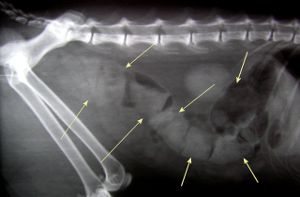

Thanks to advancements in veterinary care, our dogs and cats are living longer than ever before. This is great news! But this also means that they can develop some of the same diseases that affect older people. Osteoarthritis, also called degenerative joint disease or arthritis, can have an enormous impact on quality of life for dogs and cats. Arthritis causes pain, restricts movement, and causes joint swelling. You may first notice that your dog does not get up as easily as he used to. He may appear stiff or lame. He may lick or chew at affected joints. Signs of arthritis may not be noticed immediately.